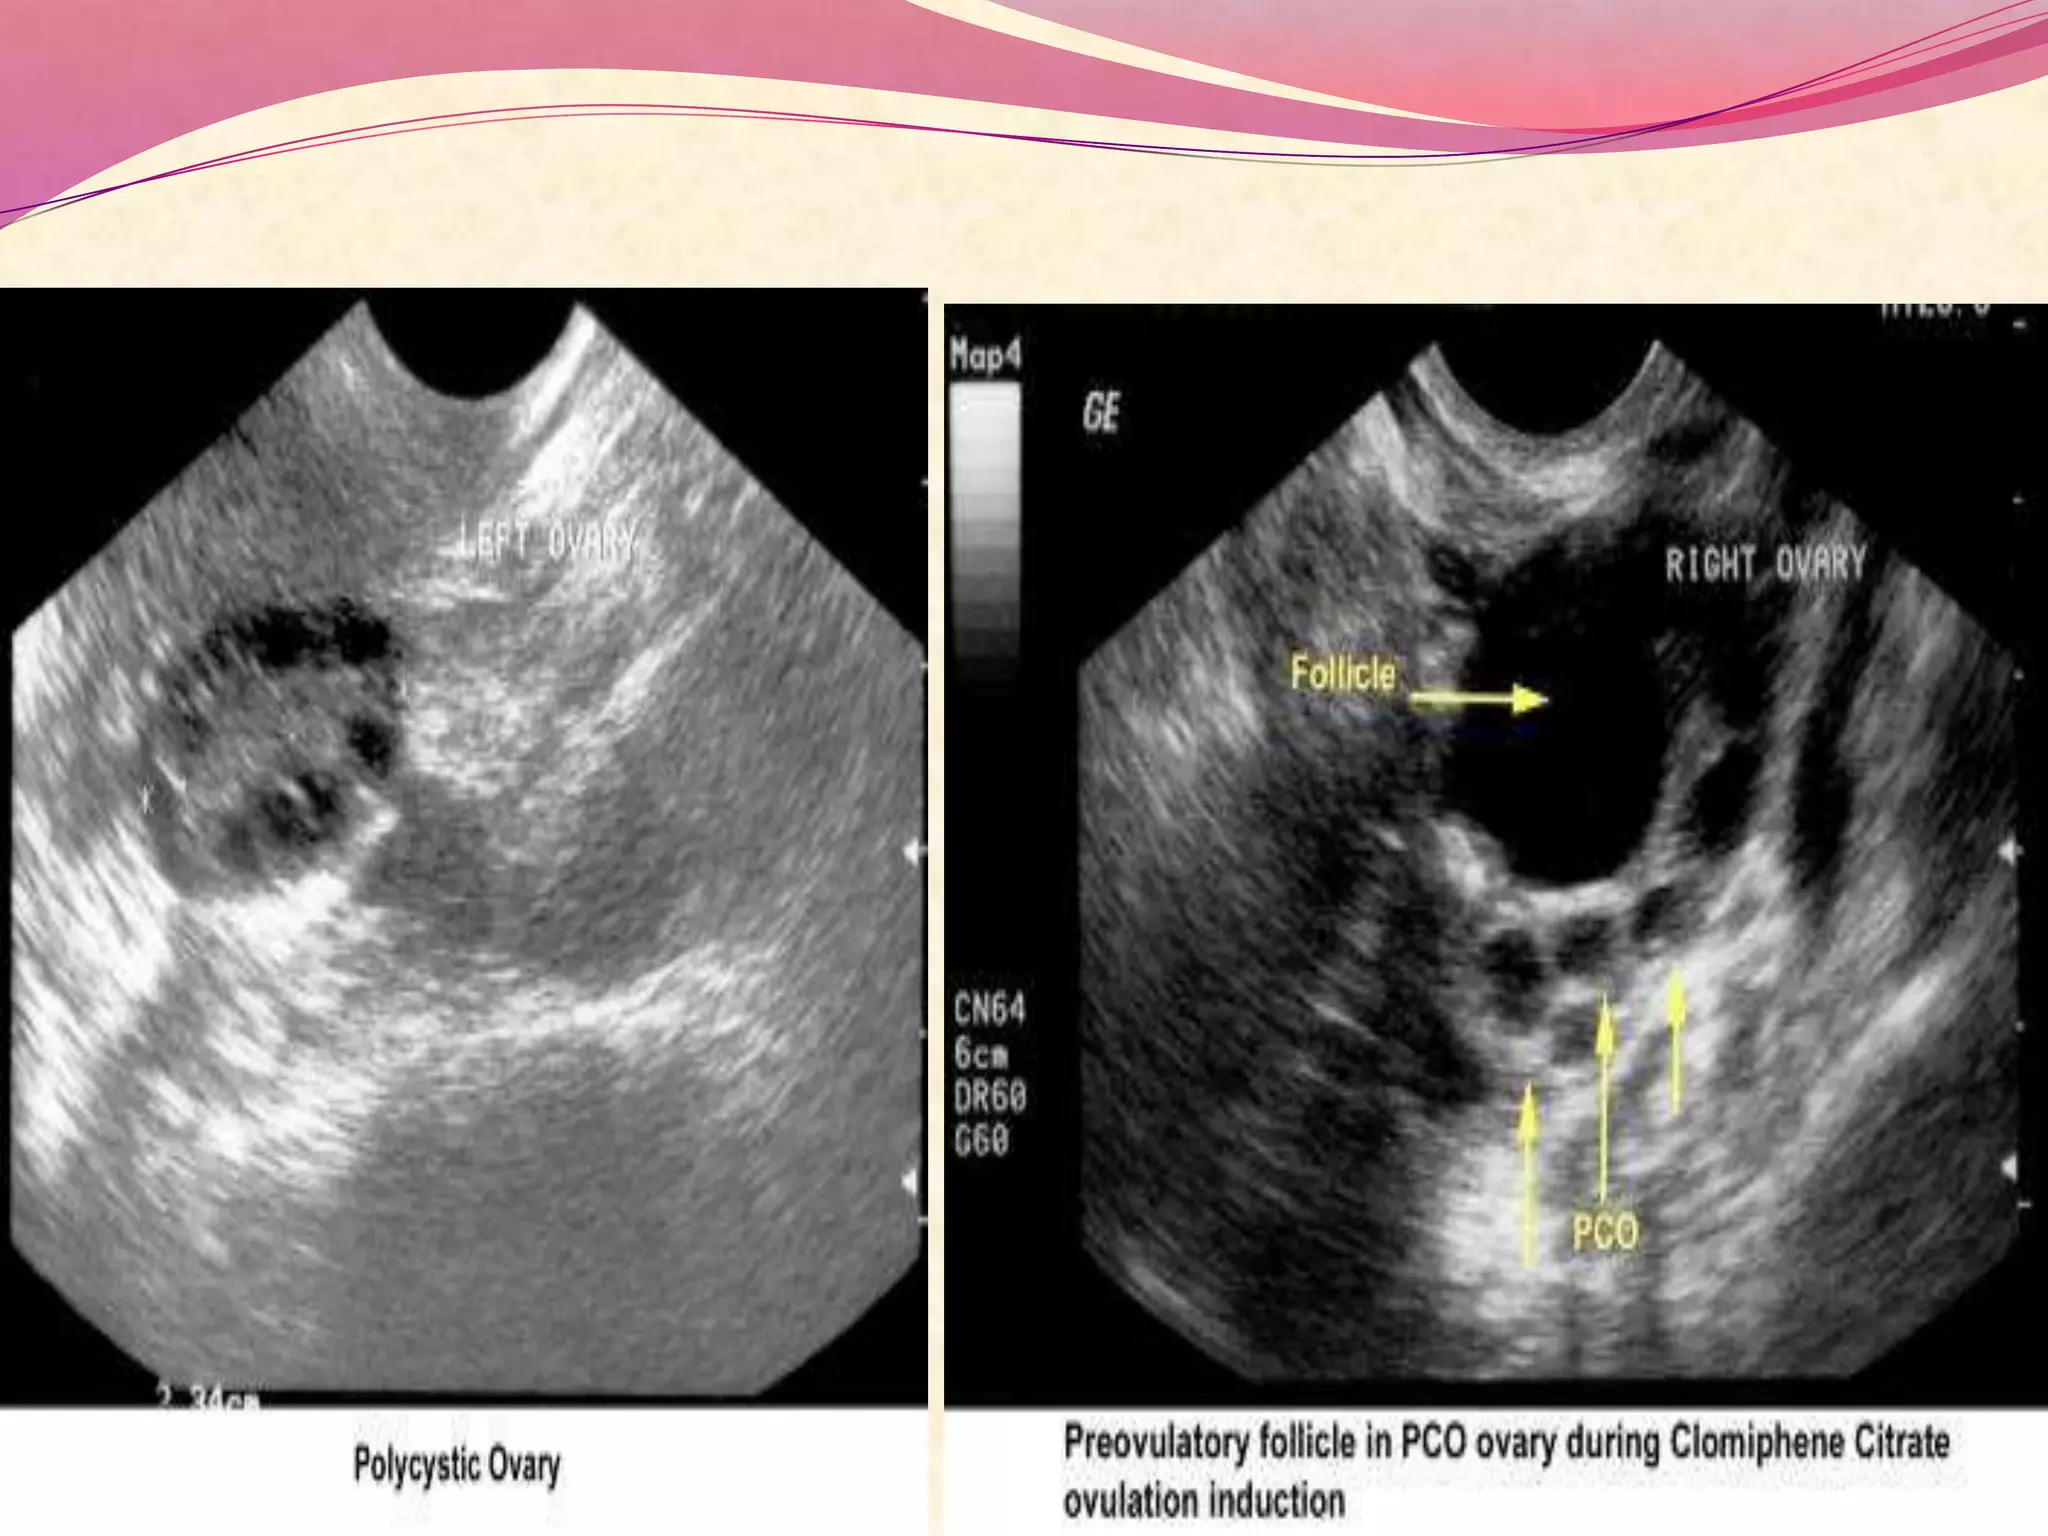

 Ultrasonography can also assist in the diagnosis of

anovulation, polycystic ovaries, and persistent

corpus luteum cysts.

 Pelvic Ultrasonography :

- Sonographic confirmation of follicle rupture with serial

ultrasonography can also be performed.